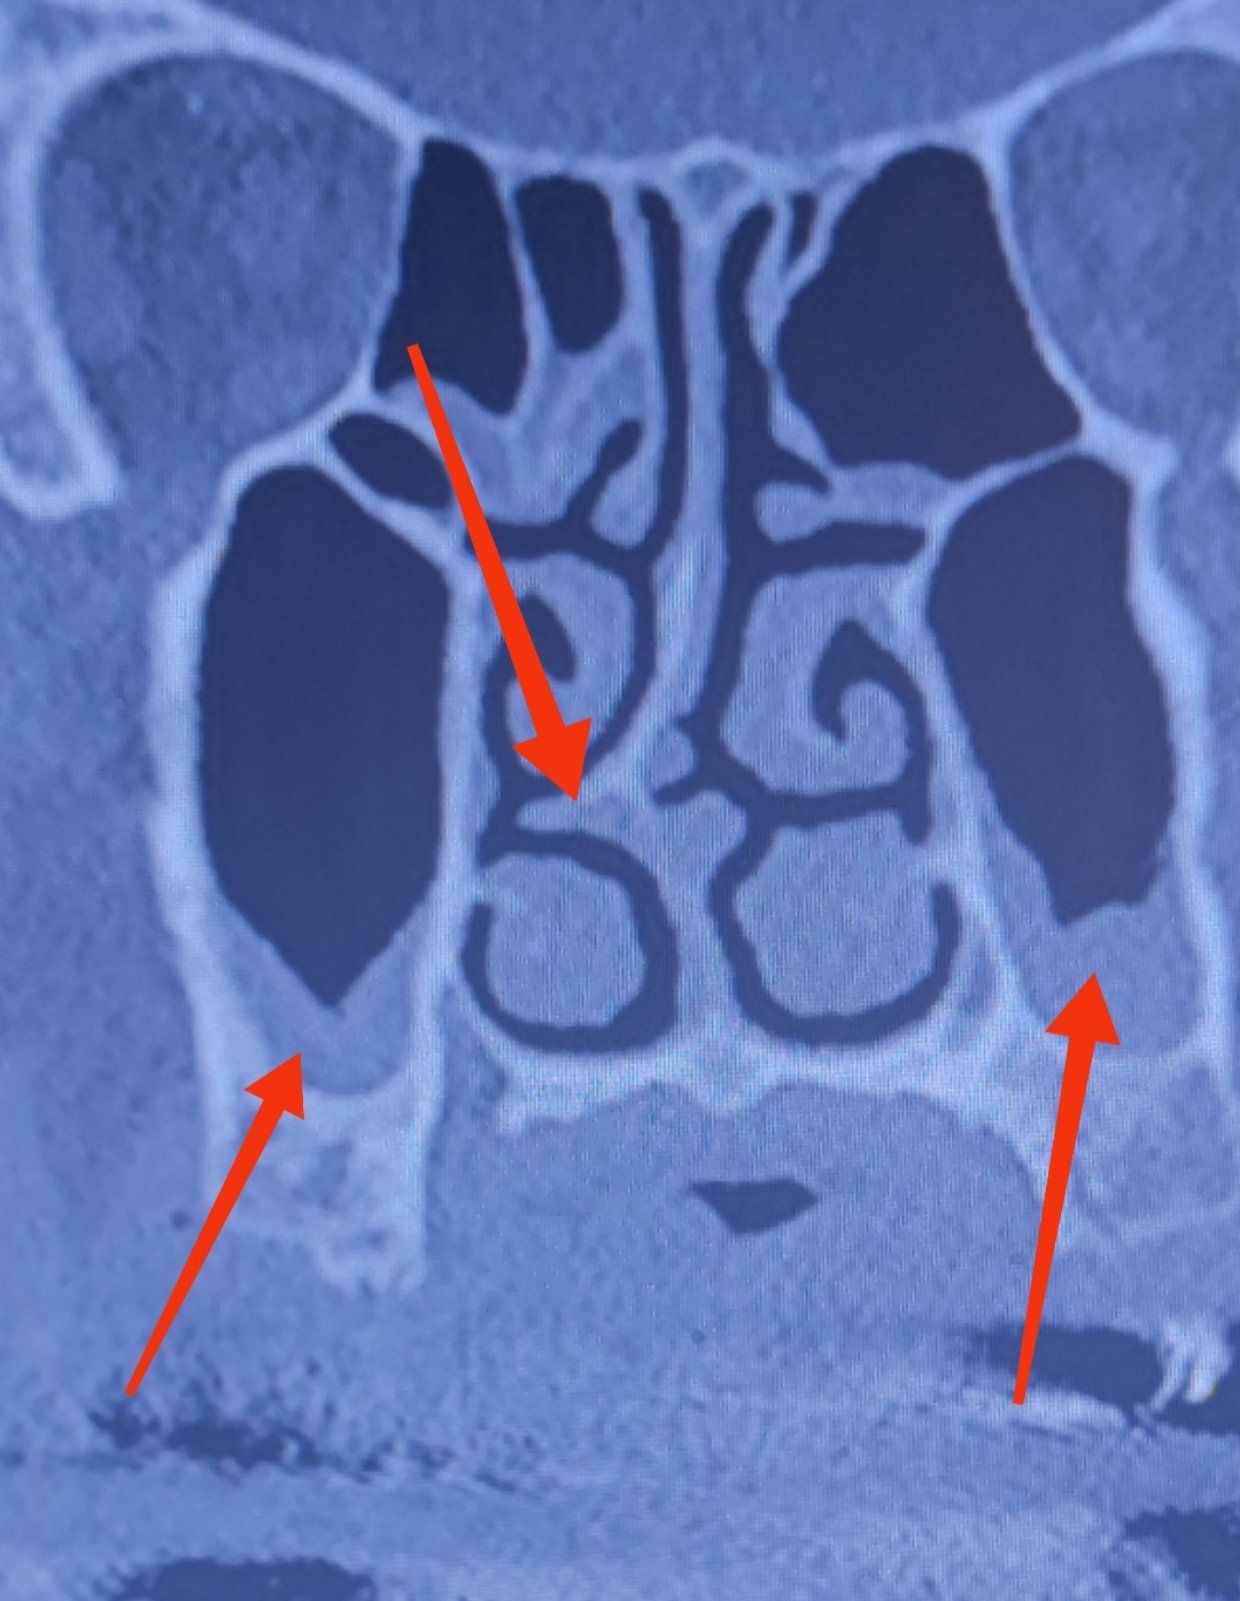

Σημαντική εξέταση για την εκτίμηση της βλάβης και την απόφαση για την περαιτέρω αντιμετώπιση είναι η αξονική τομογραφία σπλαχνικού κρανίου και τραχήλου στην οποία αποτυπώνεται το είδος, το σημείο και ο βαθμός του προβλήματος.

Τις περισσότερες φορές η διαγνωστική προσέγγιση συμπληρώνεται με την αξονική τομογραφία για τον απόλυτο και ακριβή σχεδιασμό του χειρουργείου αλλά και για την αποτύπωση του προβλήματος ( απαίτηση των ασφαλιστικών εταιρειών ).